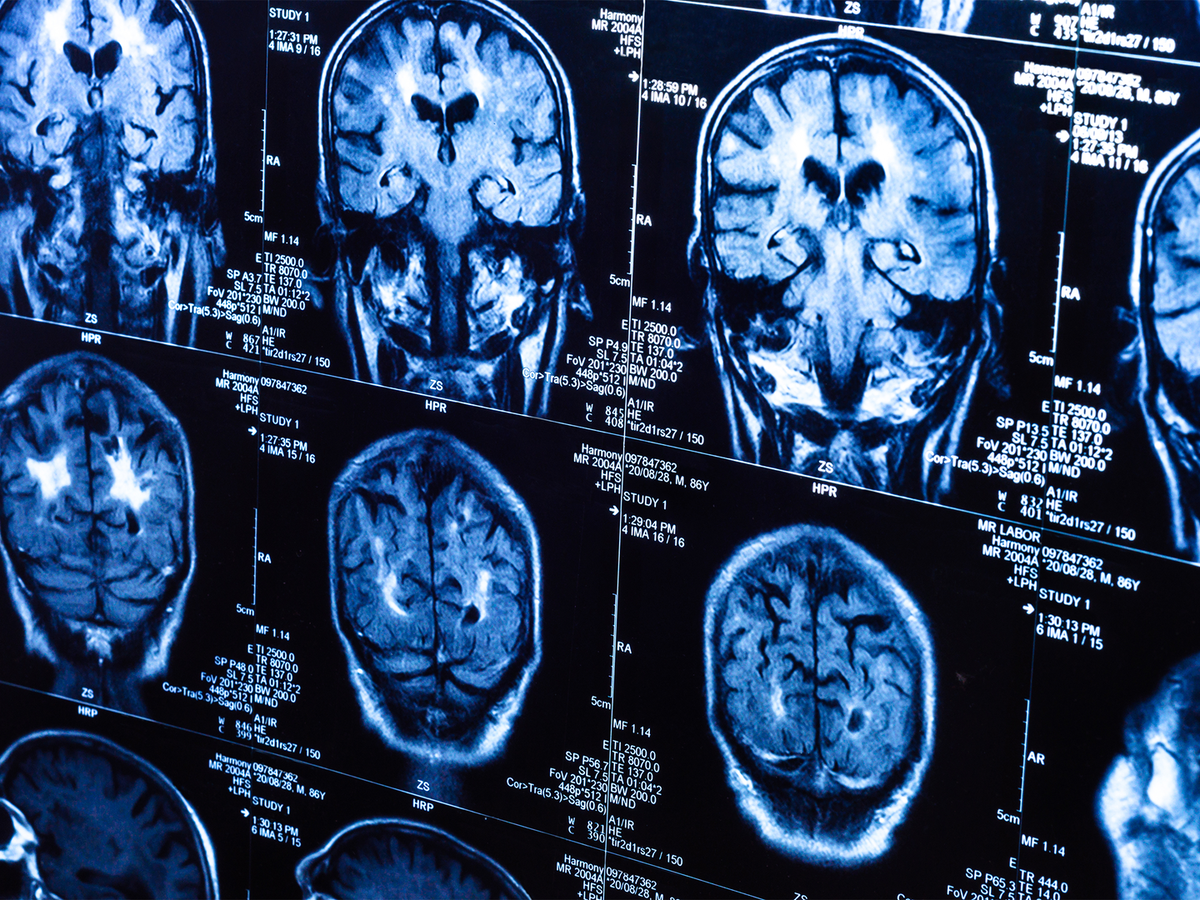

Чтобы получить более подробную картину, Готлиб и его команда сравнили снимки МРТ 163 детей, сделанные до и во время пандемии. Исследование показало, что во время блокировки COVID-19 этот процесс развития мозга у подростков ускорился. По словам Готлиба, ускоренное изменение "возраста мозга" обычно проявляется только у детей и подростков, переживших хронические неблагоприятные обстоятельства (пренебрежение семьей, насилие, семейное неблагополучие и т.д.). Подобный ранний неблагоприятный опыт может быть связан с худшими показателями психического здоровья в более позднем возрасте.